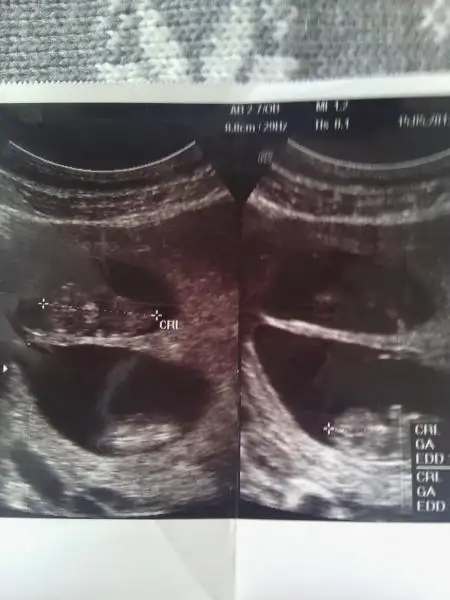

Kesin dış gebelik yok çünkü kızlarrrrrrrr

Üçüzmüş

Birisinin kesesi çok büyük

İkisinin kalp atışını duyduk))